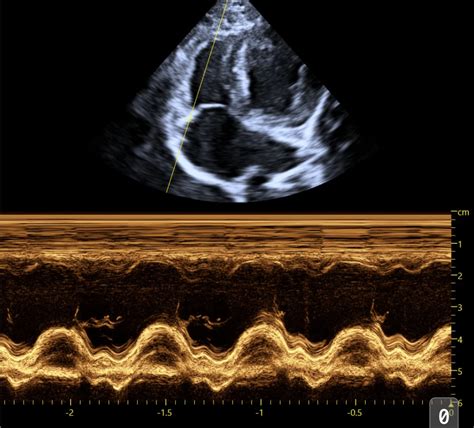

Alright, let’s start with the parasternal long-axis view , often called the PLAX. This is probably the most fundamental view you’ll learn. We get this by placing the ultrasound probe on the chest wall, typically to the left of the sternum, between the ribs. The name itself gives us clues: ‘parasternal’ means next to the sternum (breastbone), ‘long-axis’ means we’re looking at the heart lengthwise, from the base (where the great vessels exit) towards the apex (the pointy tip). In this view, you guys will see the left ventricle (LV) , the left atrium (LA) , the aortic outflow tract , and the mitral valve . We can assess the size of the LV, its wall thickness, and how it’s contracting. We can also get a good look at the mitral valve’s function and the aortic valve. This view is absolutely critical for assessing systolic function (how well the heart pumps blood out) and diastolic function (how well it relaxes and fills). We often use it to measure things like ejection fraction and fractional shortening, which are key indicators of the heart’s pumping efficiency. It’s like getting a side-profile picture of the heart’s main pumping chamber and its exit route. You can also visualize the interventricular septum and the posterior wall of the left ventricle, comparing their thickness and motion. It’s a fantastic starting point for identifying chamber enlargement, hypertrophy (thickening of the heart muscle), or dilation (enlargement). Don’t underestimate the power of this single view; it provides a wealth of information for initial cardiac assessments. We often begin our systematic scan with the PLAX, orienting ourselves before moving on to more specialized views. It sets the stage for understanding the overall cardiac architecture and function.

Next up, we have the parasternal short-axis view , or PSAX. This is like taking a slice through the heart, perpendicular to the long axis. We obtain this view by rotating the probe 90 degrees from the PLAX, still keeping it on the chest wall. The beauty of the PSAX is that it allows us to see the heart’s chambers in cross-section. We can get short-axis views at different levels : the aortic valve level, the mitral valve level, and the papillary muscle level (which is deeper in the ventricle). At the mitral valve level , we see the LV, the LA, and the two leaflets of the mitral valve appearing like a fish mouth. This is super useful for assessing mitral valve morphology and function, especially for conditions like mitral valve dysplasia or degeneration, common in older dogs. At the papillary muscle level , we see the LV cavity and the two papillary muscles within it. This view helps us evaluate the global contractility of the LV free wall and septum. And at the aortic valve level , we see the aorta , the right ventricle (RV) , and the three cusps of the aortic valve. This is great for looking for things like aortic valve stenosis or vegetation (like those nasty endocarditis growths). The PSAX is invaluable for assessing the relative sizes of the ventricles, the thickness of the ventricular walls, and the overall shape of the LV cavity. It helps us confirm findings from the PLAX and identify subtle abnormalities. It gives us a bird’s-eye view of the internal structures, allowing for a comprehensive assessment of the ventricular walls and their synchronized contraction. You can truly appreciate the circularity of the left ventricle here, which is a sign of healthy function, or an elliptical shape which might indicate issues. It’s a fantastic way to get a comprehensive understanding of the heart’s chambers and their immediate surrounding structures.